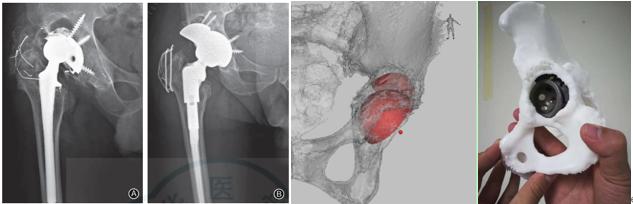

近年来,广东省人民医院关节骨病与创伤科在国内率先开展了利用3D数字骨科进行辅助关节复杂初次及翻修置换手术治疗并已广泛应用于临床。其中,术前的三维重建及手术模拟,术中的精确定位及手术导板应用均取得了满意的临床疗效和优异随访结果。在积极总结手术技巧和临床经验为患者带来福音的同时,研究团队相关研究成果多次发表于国内外骨科领域专业杂志。

目前,我科已将3D数字骨科技术常规应用于临床的复杂初次及翻修置换手术,每年完成相应高难度关节置换手术200余台。科室积极致力于应用更精准、更安全及更有效的医疗技术手段为更广大的病患服务,为大家满意的手术疗效和生活健康保驾护航。